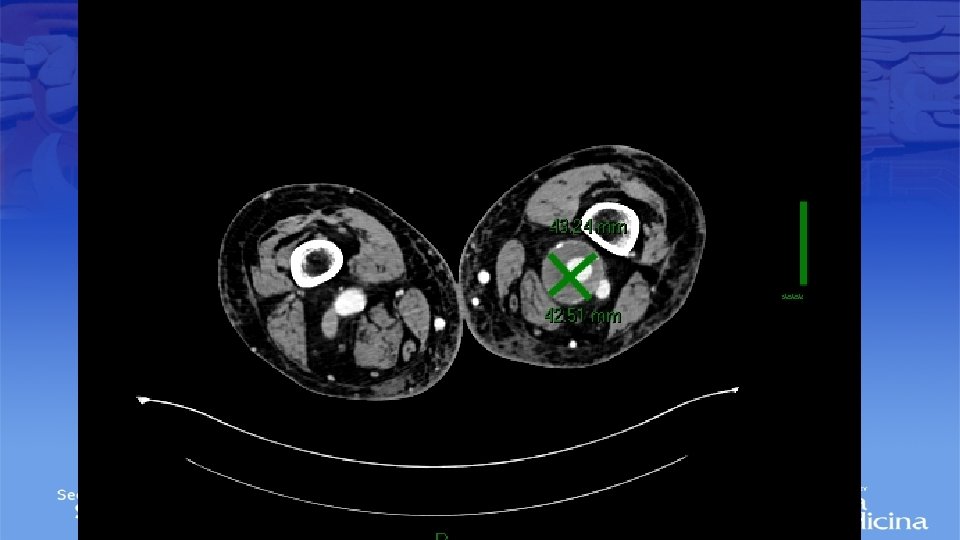

Angiotac

Impresión Diagnóstica • IDX: Aneurisma Poplíteo bilateral

Diagnostico • Ultrasonido Doppler, Angiotac, angioresonancia • Arteriografía es mas apropiada para sintomatología aguda